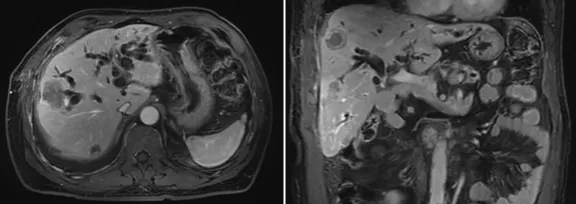

增強CT結果

image.png

壺腹部腺癌術后改變,左右肝管匯合部異常信號,不除外復發(fā)可能;考慮肝內多發(fā)轉移瘤形成

所見右側胸腔積液,右下肺片狀異常信號,建議進一步胸部檢查